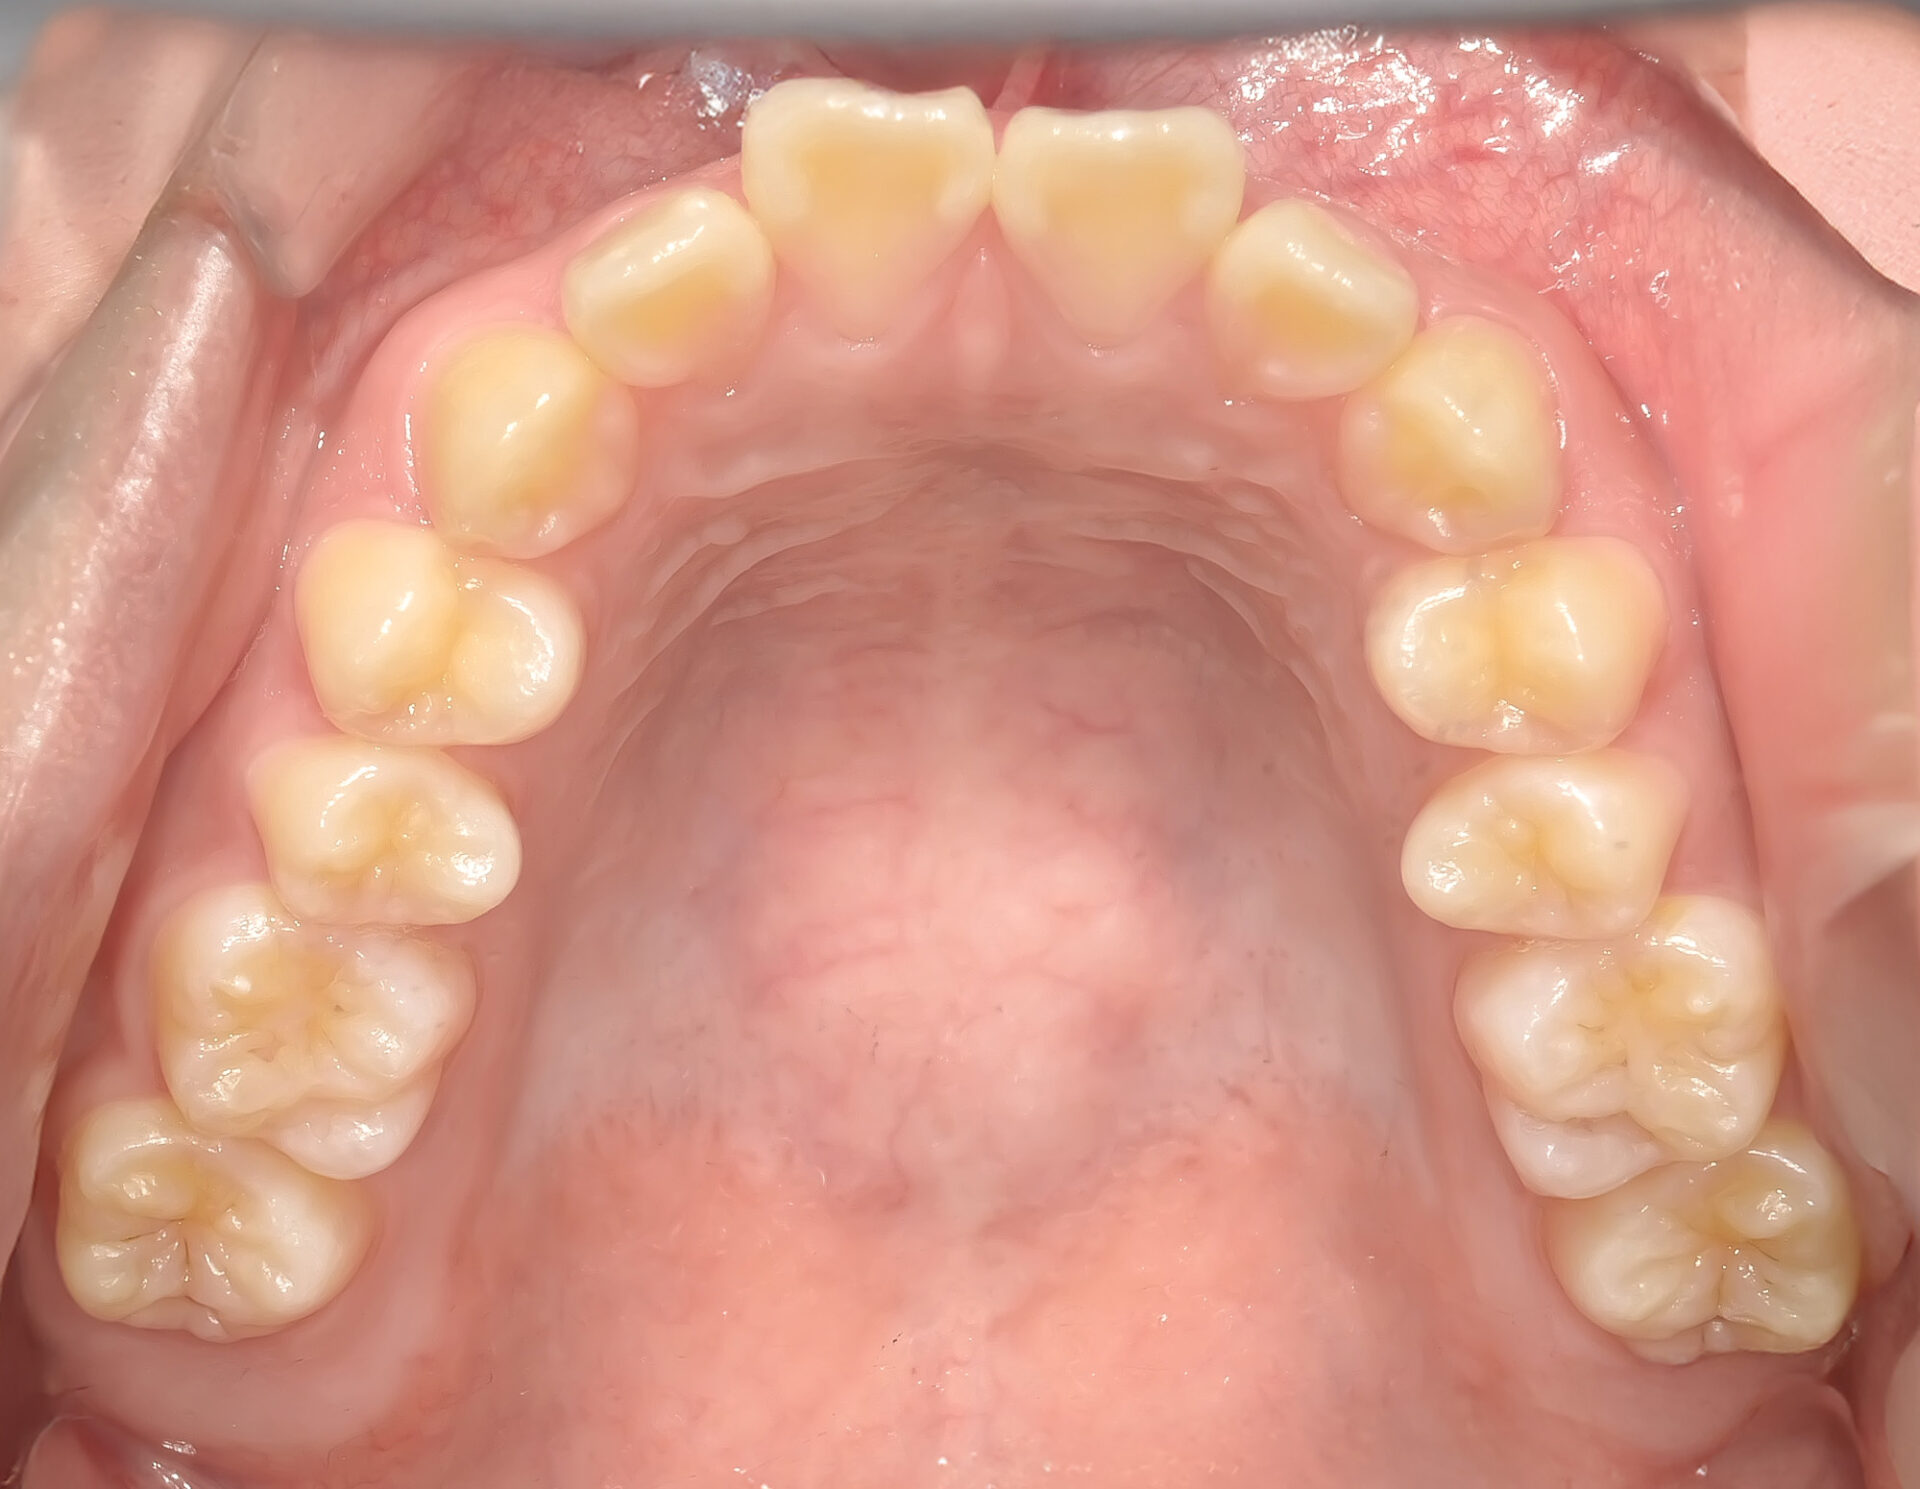

前歯2本が歯列弓(歯並びのアーチ)から外側に出ています。

上顎に装置を装着した状態。

左右の前から4番目の歯を抜き、前歯を中に入れるスペースメイクを行います。

ワイヤーの超弾性(元の形に戻ろうとする力)が歯を並べます。